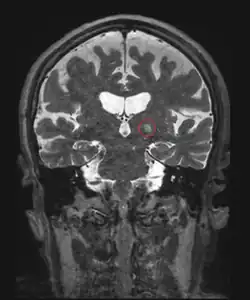

Another invasive surgical treatment of essential tremor is deep brain stimulation (DBS). DBS is a surgical procedure that involves the placement of a permanent electrode with 4-8 contacts within the brain with connecting wires connected to a pulse stimulator implanted near the patient's collarbone.[65] In the treatment of tremor, the electrodes are placed in the ventral intermediate nucleus (Vim) of the thalamus.

The pulse stimulator delivers constant electrical pulses to the target area, which interfere with activity of the target area, which has been shown to improve tremor symptoms.[83] At one year following the surgical intervention with DBS, patients showed 66% improvement and 48% improvement at 10 years.[72] DBS is considered an effective surgical treatment of ET, but there are associated side effects and complications that have been reported with DBS in clinical trials, including imbalance or gait instability, dystonia, paresthesia, hemorrhage.[71]